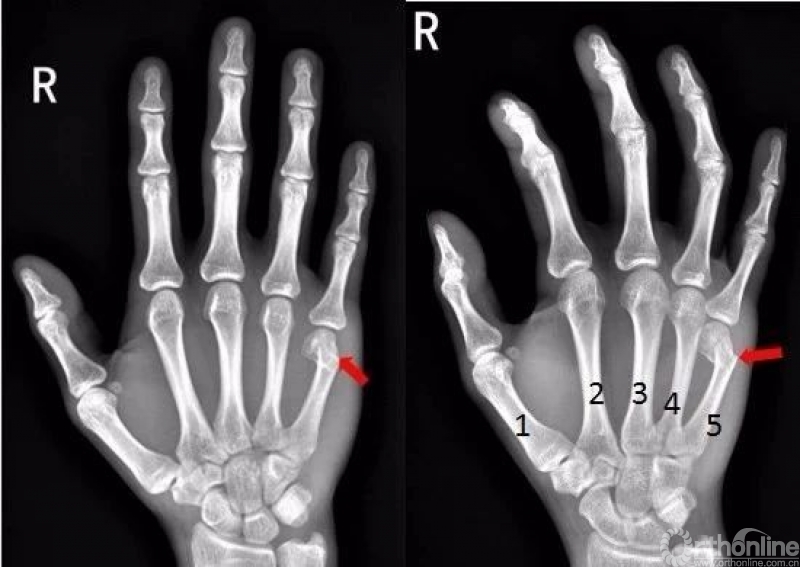

手

右手拇指远节指骨甲粗隆游离骨碎片影

右手拇指末节指骨见数条骨折线,骨折端对位对线尚可右手拇指末节指骨粉碎性骨折

右手拇指近节远端见斜行骨折透亮线,断端稍分离移位,右手拇指近节远端骨折

右手中指远节近端背侧关节处见游离骨片影。右手中指远节骨折

右手第五掌骨远端骨皮质不连续,骨折端移位、成角。右手第五掌骨骨折(1-5. 第1-5掌骨)